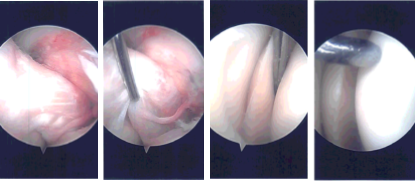

There was a complex tear of the posterior horn and body of the medial meniscus down to medial surface as well as the lateral free margin. Debridement of the tear was done with the use of biter as well as shaver and a stable margin was achieved.

Examination of the intercondylar notch showed intact ACL. Examination of the lateral tibiofemoral compartment showed intact cartilage as well as meniscus. Examination of the patellofemoral compartment showed intact cartilage and normal patellar tracking.

The arthroscope was inserted from the medial entry portal and the margin of the medial meniscus was cleaned to a balanced margin. Final pictures were taken and saved.

Intraoperative Arthroscopy Images